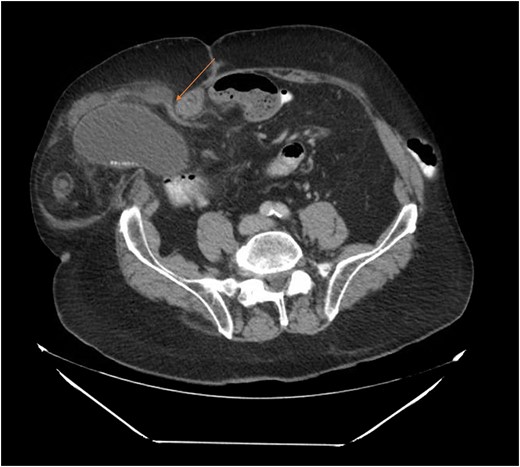

Our patient is an 89-year-old male with a history of a Hartmann’s procedure (2006) for Crohn’s disease of the sigmoid colon followed by a reversal of the colostomy with a diverting loop ileostomy (2008). Due to his comorbidities and age, the patient declined further surgery to reverse his loop ileostomy. Most recently, the patient presented to the emergency room with no ostomy output for the past 14 h, nausea and frequent burping. He reported a burning sensation around his ostomy. His physical examination revealed a large parastomal hernia in the right hemiabdomen and associated tenderness in the right upper quadrant, with no overlying skin changes. His white blood cell count was 8.1 (82.4% neutrophils), and he had normal liver function tests. A computed tomography (CT) scan of the abdomen and pelvis revealed a large parastomal hernia with a wide neck containing a distended gallbladder concerning for acute cholecystitis, as well as a small bowel obstruction with a transition point at the level of the hernia (Figs 1 and 2). A previous CT scan showed the same hernia with a nondistended gallbladder and non-obstructed bowel entering and exiting the stoma (Fig. 3).

CT from current admission with distended gallbladder consistent with acute cholecystitis.